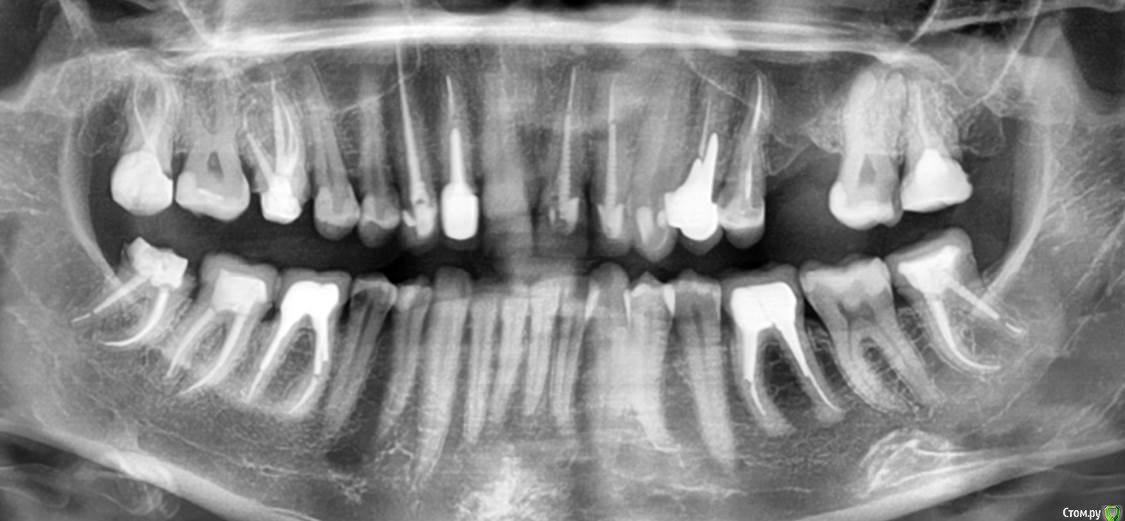

Л Ю С Я Опубликовано 5 декабря, 2016 Поделиться Опубликовано 5 декабря, 2016 Полечили гаиморит без ЛОР. Срок наблюдения 6 месяцев. Теперь на очереди 2.7 5 Ссылка на комментарий

Л Ю С Я Опубликовано 5 декабря, 2016 Поделиться Опубликовано 5 декабря, 2016 КлассДа, очень показательно. Хотя пациентка сначала не верила в успех, поэтому от лечения 2.7 отказалась. 10 лет мучений, не знаю ,почему лор не заподозрил одонтогенный. Пришла начитавшись Интернета про причины гайморита. Видимо не зря читала))) Ссылка на комментарий

Л Ю С Я Опубликовано 5 декабря, 2016 Поделиться Опубликовано 5 декабря, 2016 Все стандартно, растворы хлорка, эдта,апексы пал-50, бук-40-45, от рд -0.5, кальций был 2 раза, петенси получено везде,первый раз во время обработки случайно вышла за апекс небного, как полилось.. ((((Минут 30 сопли. Симптомы ушли. Задышала. Через 2 недели как то влажно, ещё кальций, через 2 недели постоянная обтурация : пал- сквирт, бук- волна. Перед обтурацией ХГБ. Пациентка от коронки категорически отказывалась, сделали композитный оверлей. Сейчас собираемся перебирать 2.7, потом все равно заставлю коронки сделать. Кстати, заметила, если эндо сделано удачно, в пазухе достаточно быстро все восстанавливается 1 Ссылка на комментарий

ger_berra Опубликовано 5 декабря, 2016 Поделиться Опубликовано 5 декабря, 2016 Внимательно почитайте нашу дискуссию.....там изложен... мой случай, с описанием... и КТНе хочу повторяться.. если коротко, при лечении зубов с воспалением...прилежащих к гайморовой пазухенеобходимо учитывать , Характер воспаления( Первичное или хроническое) Топографию (положения корней зубов).. Степень вовлеченности в воспаление, пазухи ( Локальное увеличение слизистой или полное ) Сопутствующие а именно риногенные проблемы гайморовой пазухи ( Анатомия, микробиология и т.д.)Учитывая все ниже сказанное, процент удачного эндолечения ... будет ниже.чем в других участках, а неудачи могут привести к серьезным осложнениям, в синусе. Я редко захожу на форум и не все темы читаю.Но этот пост меня зацепил своей безрассудностью на фоне множества контраргументов.Характер воспаления в синусе ( первичное или хроническое ) Абсурд.Какая разница ? В первую очередь нужно определить- причина зуб или нет. Это раз.Топография. Правильно Люся сказала,что если стоматогенный синусит имеет место быть,значит надо с зубом решать проблемы.Если периодонтит лечибельный,то лечим по протоколу. Это два.Степень вовлеченности пазухи.Тут вообще трэш,господа! Для кого-то до сих пор секрет,что чем больше еды в канале для флоры,тем больше радиолюценция? Касаемо верхнечелюстного синуса: от одного необработанного МБ2 канала бактериальные токсины дают такой мощный иммунный ответ,что вся пазуха закрыта эксудатом! А если в процессе инструментации проткнуть файлом "незначительную гранулёму",то это на КЛКТ даёт так называемый "уровень жидкости",то есть просветление ,имеющее четкие горизонтальные границы в корональной и саггитальной плоскости.Это три.Сопутствующие риногенные проблемы стоматолог обязан дифференцировать и ,если мопед не его,то отправлять к ЛОРикам. Это четыре.Учитывая все ниже сказанное, процент удачного эндолечения ... Работайте с грамотными эндодонтистами и не спешите всё удалять,имплантирвать,резать и футболить к ЛОРам. 3 Ссылка на комментарий